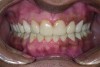

Figure 19. Postoperative frontal smile.

Figure 19

The final restorations depicted restoration of form, function, and beauty, with good harmony of restoration and the periodontium (Figure 19 through Figure 25). MIP was in harmony with CR, and right and left lateral excursion discluded all posteriors with anterior group function. The postoperative orthopantomogram (OPG) (Figure 26) shows the treatment done while maintaining the vitality of anterior teeth.